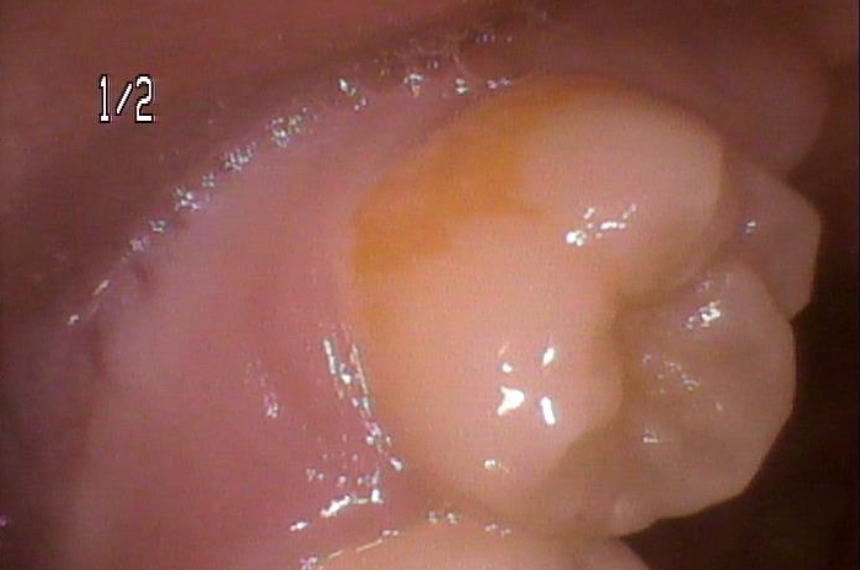

この写真は上の12歳臼歯といって、名前の通り12歳くらいで生えてくる第二大臼歯という永久歯なのですが、オレンジ色に変色している部分がお分かりになるかと思います。

このオレンジ色の塊は、歯垢から歯石へと移行する途中の状態です。

上の左側の写真のオレンジ色の周りに歯垢や歯石が歯と歯の間、歯と歯茎の境目に溜まっているのが見えます。

このオレンジの塊は、12歳臼歯の様な上の奥歯の外側(ほっぺた側)や、下の奥歯の内側(舌側)、上の前歯の歯と歯茎の境目、奥歯の咬み合わせの面の小窩裂溝と呼ばれる溝の部分などにつきやすく、大人になってからよりも子供の時期によく見られるのが特徴です。